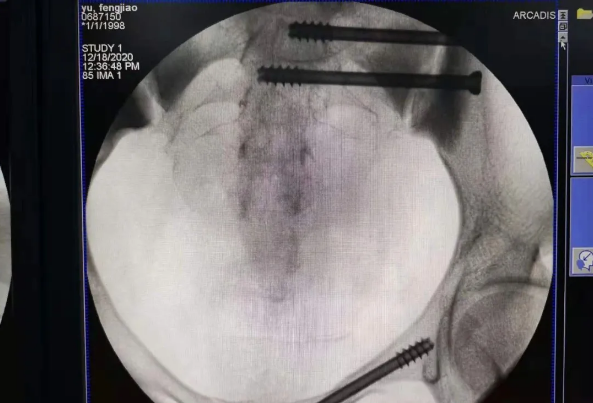

在南昌市第一医院廖琦教授向导下,由创伤骨科团队借助天玑?骨科手术机械人为患者“量身定做”最理想、最清静的教科书般的通道,完善清静微创完成手术,并且手术时间显着缩短,真正做到“指哪儿打哪儿”!更让患者定心的是,天玑?骨科手术机械人的“稳固手”机械臂举行精准定位,不必重复探寻。

由于天玑?骨科手术机械人的精准及高效,可以使手术时间显着缩短,因此在骨盆骨折手术后,在廖琦教授指导下,脊柱外科团队使用天玑?骨科手术机械人同样为20岁女性腰椎骨折患者“量身定做”最理想、最清静的教科书般的通道,完善清静微创完成手术,手术不但时间缩短,并且出血和透视镌汰。